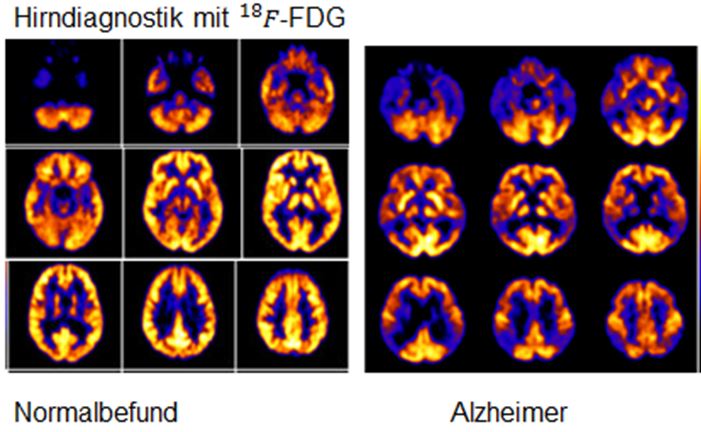

- Neurologie: Die PET-CT-Untersuchung des zerebralen Glukosestoffwechsels ist die empfindlichste Methode zur Frühdiagnostik von Demenzen. Sie kann zudem verschiedene Demenzformen differenzieren. Die PET-CT kann Epilepsie nachweisen. Epilepsieherde im Hirn zeigen zwischen den Anfällen im PET-CT einen reduzierten Glukosestoffwechsel.